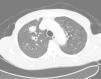

His general physical and systemic examination except for knee crepitus in both knees was otherwise normal. His laboratory examination including a complete blood count, basic chemistry and liver function tests including a clotting profile was normal. No abnormality was seen on an electrocardiogram and pulmonary function tests. On routine investigation his chest X-ray revealed a pulmonary nodule in the right upper lobe. His CT scan of the chest (see Figs. 1 and 2) showed pulmonary nodule 2cm×2cm in size.

It was decided to follow up the patient with close monitoring and repeat radiological imaging. He was recalled again in two months. Since progression of the nodules was suspected (Figs. 3 and 4), a PET scan was performed on this occasion to see any uptake (see Fig. 5).

Follow-up CT scan same level as Fig. 2.